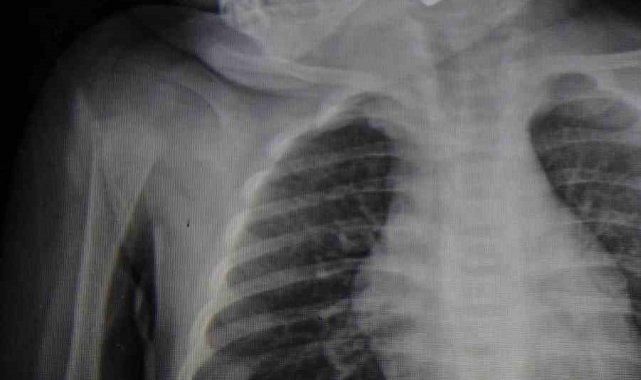

Yaşanan olayla ilgili bilgi veren Doç. Dr. Mehmet Uysal, "Acil polikliniğimize kusma şikayeti ile 6 aylık bir kız bebek getirilmiş ve bize haber verildi. Biz de vakit kaybetmeden geldik, hastamızı gördük. Yapılan tetkikler sonucunda, ağız tabanına oturan ve yemek borusunun birinci darlığına kadar uzanan, kumanda pili dediğimiz bir pille karşılaştık. Filmde ve muayenede bunu gördük. Hastayı ilk gördüğümüzde bayağı siyanotik durumda, solunum sıkıntılıydı ve oksijen satürasyonu 90 civarındaydı. Böyle olunca bir an önce beklemeden hızlı bir şekilde ameliyathaneye götürdük. Orada ameliyathanedeki anestezi uzmanlarımız ve personel bize yardımcı oldu, hasta hızlı bir şekilde entübe edildi. Ondan sonra da laringoskop ve magill forseps dediğimiz malzemelerimizle bu yabancı cismi çıkarmış olduk. Bir an evvel müdahale ettik, iyi ki müdahale ettik, orada ağız tabanında, özellikle ön kısmında hasar oluşmuştu. Müdahale sonrasında da hastanın solunum problemleri bir süre devam etti, bu yüzden 24 saat takip ettik. Herhangi bir problem oluşmayınca 24 saat sonra kontrole gelmek üzere hastayı taburcu ettik" diye konuştu.